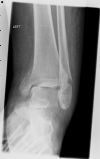

Left Ankle Trimalleolar Fracture - lateral view (2)

Click here to view image

Left Ankle Trimalleolar Fracture - AP view (1)